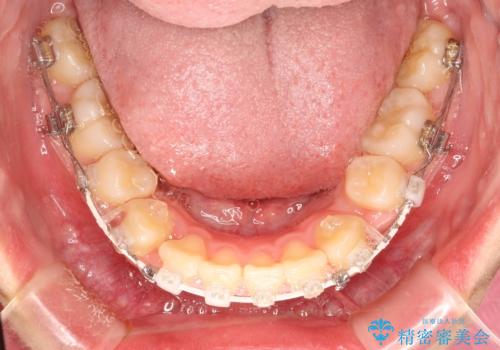

- 矯正装置

- 審美装置

- 上下左右4本の小臼歯を抜歯、ラビアル・ワイヤー矯正を計画した。

抜歯をして第1小臼歯分のスペースを獲得することにより、ガタつきの改善と前歯のリトラクトをおこない、横顔の印象もすっきりとし、整ったEラインを作ることができました。